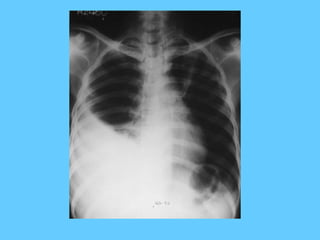

• Extensive pulmonary oedema

• Terminal stages of a failing left ventricle

Extensive pulmonary oedema

• Bat’s wing shadow –Pulmonary oedema